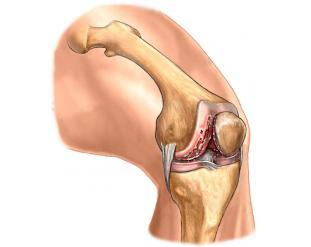

- zwyrodnienia stawu kolanowego, barkowego

- leczenie uszkodzeń chrząstki stawowej i uszkodzeń wewnątrzstawowych